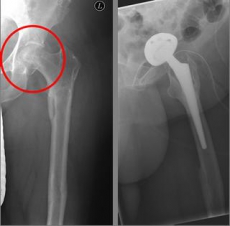

Picture: In this case, there was already a wear of the hip joint and the affected patient was relatively young, so that a cement-free total endoprosthesis (TEP) of the hip was selected for the treatment of the femoral neck fracture. Here, in addition to the femoral head, the acetabular cup was replaced by an implant.

In older age and with stronger displacement of the fracture can be done by a duo-head prosthesis. Here only the femoral head is replaced, the hip socket is preserved. In case of simultaneous hip arthrosis, a total endoprosthesis (hip replacement) with replacement of the acetabular cup can be used.

Picture: This picture shows the treatment of a severely displaced fracture with a so-called duo head prosthesis. The acetabulum was left here.